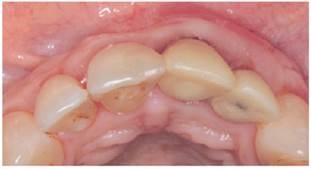

La zona en relación a las recesiones a tratar fue anestesiada con articaína 4% (Septanest®), y luego las superficies radiculares fueron pulidas con cureta Gracey Mini-five 1-2 (Hu-Friedy®). Posteriormente, se realizó una incisión vertical de acceso (hoja 15c Hu-Friedy®) sobre el frenillo medio superior, para lograr un acceso a ambos cuadrantes del maxilar. Esta incisión se realizó con el fin de elevar un colgajo mucoperióstico11 a nivel de encía adherida mediante un tunelizador (TKN2 Hu-Friedy®), alcanzando la zona intrasurcular de piezas 1.4 a 2.4. Posteriormente, a nivel del límite mucogingival, se comenzó a elevar un colgajo mucoso, con el fin de permitir el desplazamiento del colgajo a coronal (fig.2). Una vez eliminada la tensión del colgajo, se procedió a medir la extensión del tejido necesaria para injertar la zona receptora del lado izquierdo y así obtener un injerto libre palatino del lado izquierdo. Se obtuvo injerto libre, ya que permite conseguir un conectivo de mejor calidad y requiere de una técnica menos compleja de obtención. Luego de obtenido, se colocó cemento quirúrgico en la zona dadora, y el injerto se desepitelizó con una hoja de bisturí nueva (hoja 15c Hu-Friedy®). Para posicionar el ITC y el Mucograft® en sus respectivos sitios, se introdujo una sutura reabsorbible multifilamento 5/0 (Safil®) sobre encía adherida en distal de la recesión más distal a injertar de cada lado y se pasó por la incisión vestibular realizada sobre el frenillo medio superior. Luego, la sutura se pasó por el borde de cada injerto y se volvió realizando el camino inverso al de entrada, traccionado el injerto para luego suturarlo en distal y mesial. Una vez posicionado el ITC en la zona receptora del lado izquierdo (pd 2.1 a 2.3) y el Mucograft® en la zona receptora del lado derecho (pd 1.1 a 1.3), el colgajo se desplazó 2mm coronal al LAC, intentando llegar al nivel más coronal de la papila interproximal, fijándolo mediante sutura suspensoria. Para esta técnica de sutura y tracción coronal del colgajo, se realizó un punto simple (sutura reabsorbible multifilamento 5/0, Safil®) 2-3 mm apical al margen gingival de cada diente a tratar, abarcando el ancho del diente. Se acondicionó la cara vestibular de cada diente, en el centro de la corona, con ácido ortofosfórico al 37% por 5 segundos, se lavó con suero y se secó. La sutura fue posicionada y adherida a la cara vestibular de cada pieza con composite (Flow z350 3M®), sin utilización de adhesivo. Posteriormente, la incisión vestibular sobre el frenillo medio superior, se suturó con sutura reabsorbible multifilamento 5/0 (Safil®) (fig.3).